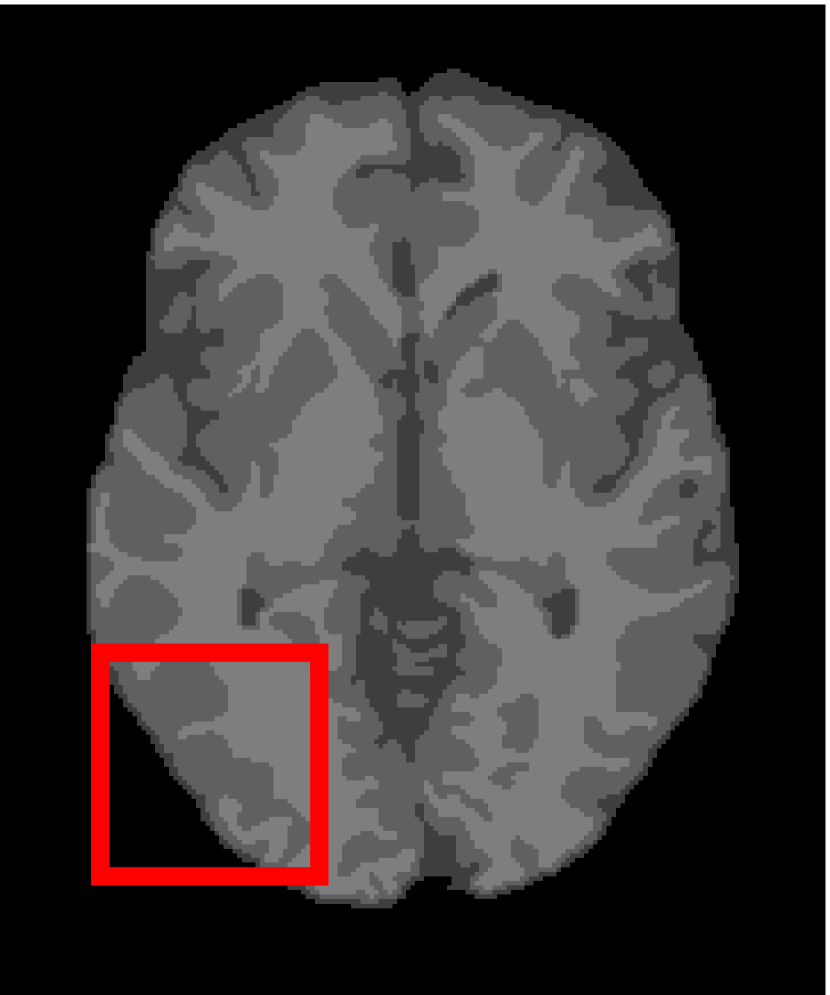

Next, we representatively segment five medical images from BrianWeb. They are represented as five slices in the axial plane with a sequence of 70, 80, 90, 100 and 110, which are generated by T1 modality with slice thickness of 1mm resolution, 9% noise and 20% intensity non-uniformity. Here, we set c=4𝑐4c=4 for all cases. The comparison between WRFCM and its peers are shown in Fig. 9 and Table II. The best values are in bold.

Figure 9: Segmentation results on five medical images. The parameter: ϕ=5.35italic-ϕ5.35\phi=5.35. From top to bottom: noisy images, ground truth, and results of FCM_S1, FCM_S2, FLICM, KWFLICM, FRFCM, WFCM, DSFCM_N, and WRFCM.

By a view of the marked red square in Fig. 9, we find that FCM_S1, FCM_S2, FLICM, KWFLICM and DSFCM_N are vulnerable to noise and intensity non-uniformity. They give rise to the change of topological shapes to some extent. Unlike them, FRFCM and WFCM achieve sufficient noise removal. However, they produce overly smooth contours. Compared with its seven peers, WRFCM can not only suppress noise adequately but also acquire accurate contours. Moreover, it yields the visual result closer to ground truth than its peers. As Table II shows, WRFCM obtains optimal SA, SDS and MCC results for all five medical images. As a conclusion, it outperforms its peers visually and quantitatively.